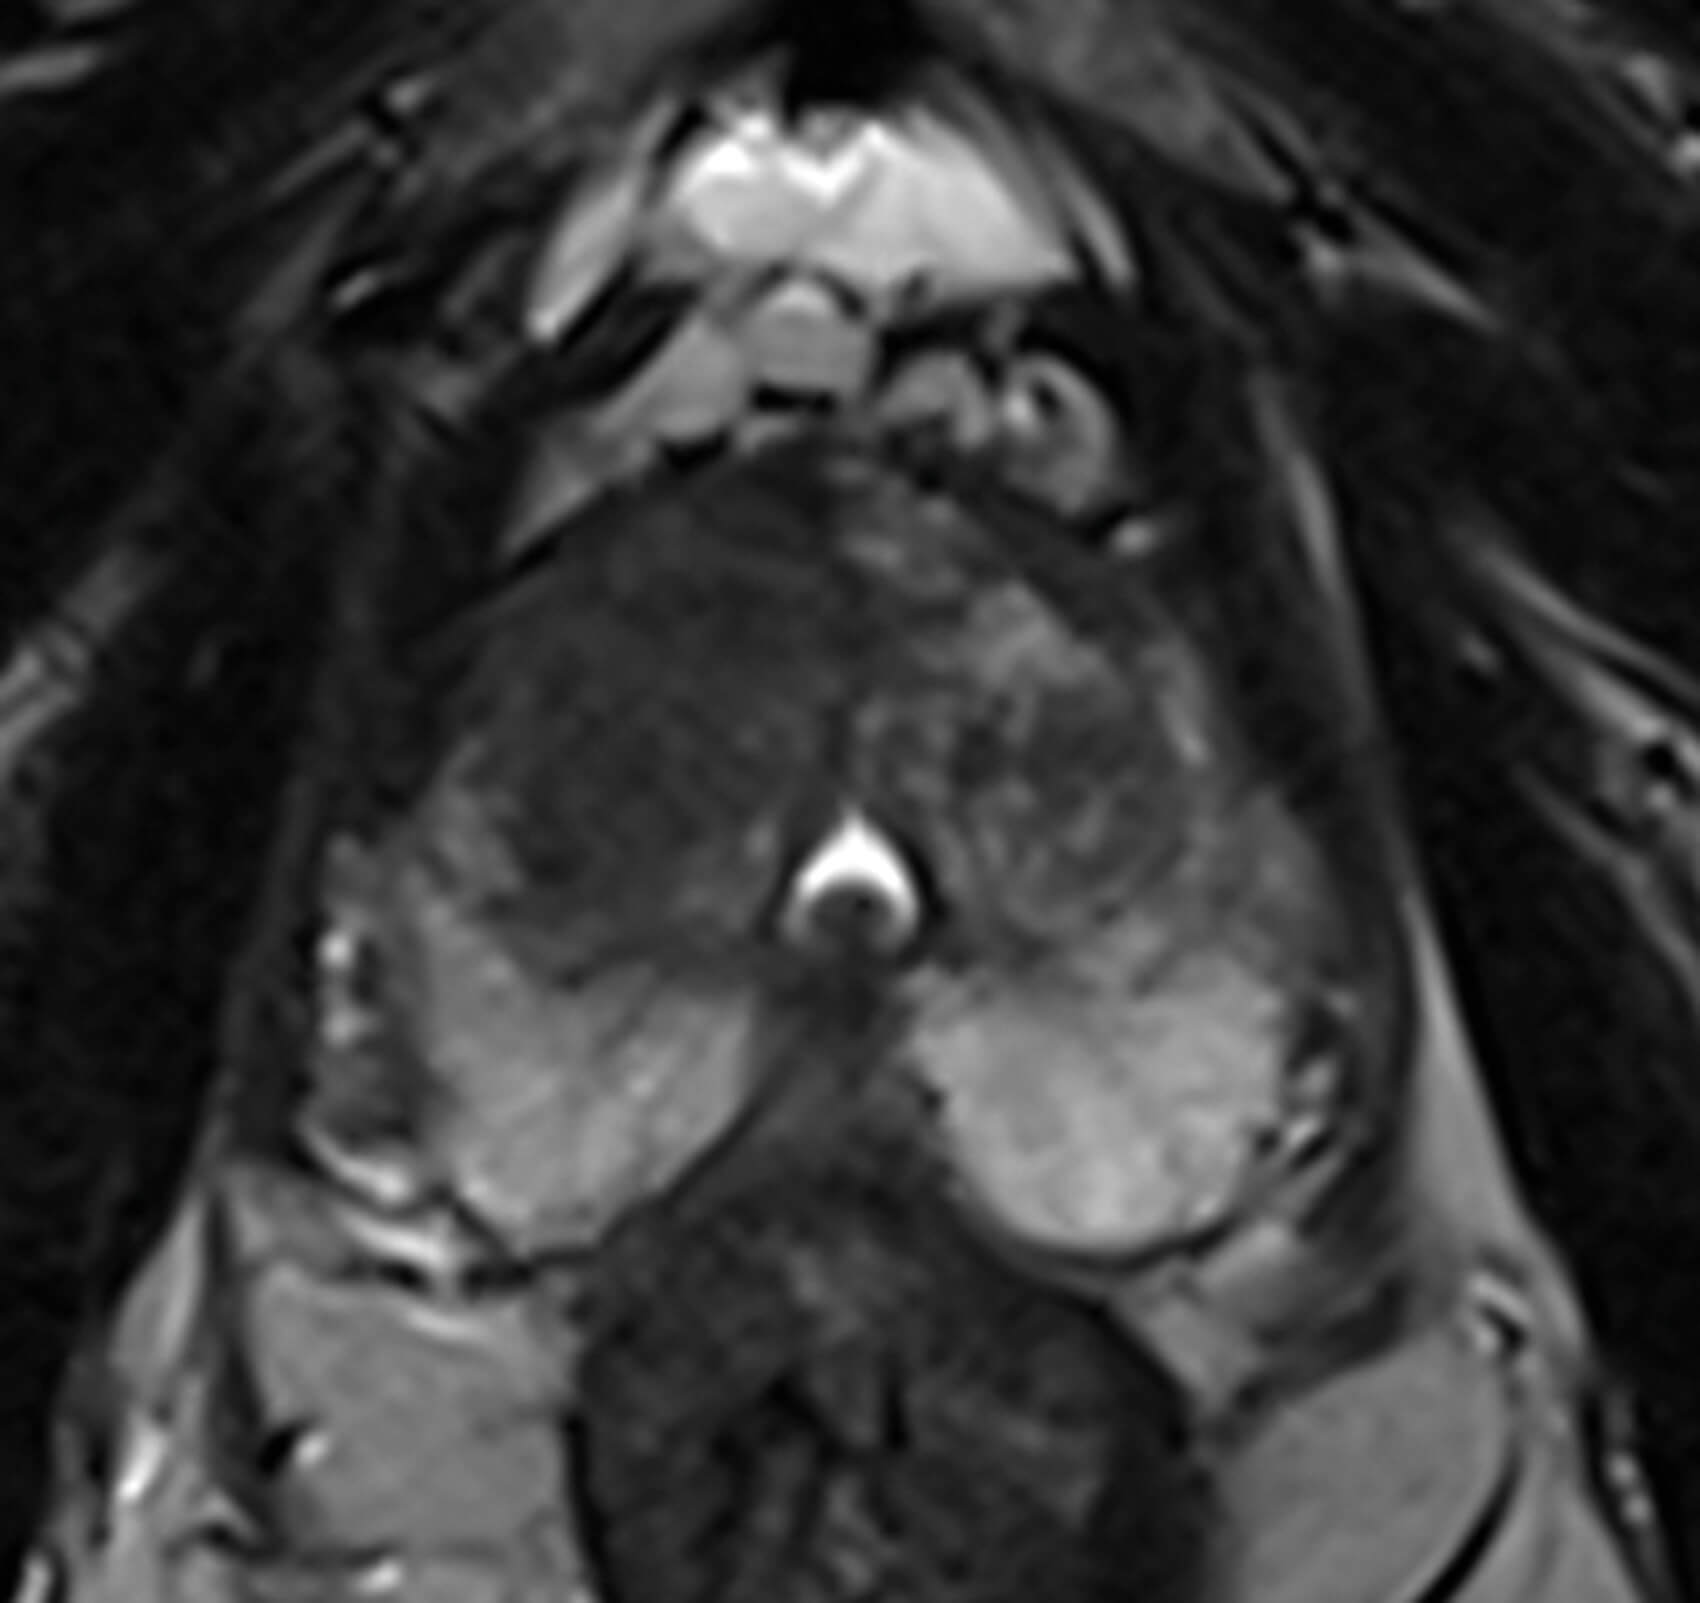

Figure 1.

1 .Image 1 is the axial T2-weighted image of a PI-RADS 5 mid-gland lesion in the right transition zone. The lesion appears dark, measuring 19mm in diameter and would be T2bN0M0. Image 2 and image 3 is the same lesion demonstrated on the high b value (b1400) Diffusion weighted image (DWI) and the apparent diffusion coefficient (ADC) map respectively. Image 4 shows the same lesion with increased contrast uptake on the early dynamic contrast enhanced sequence (although contrast has limited role in the evaluation of the transition zone) [1].